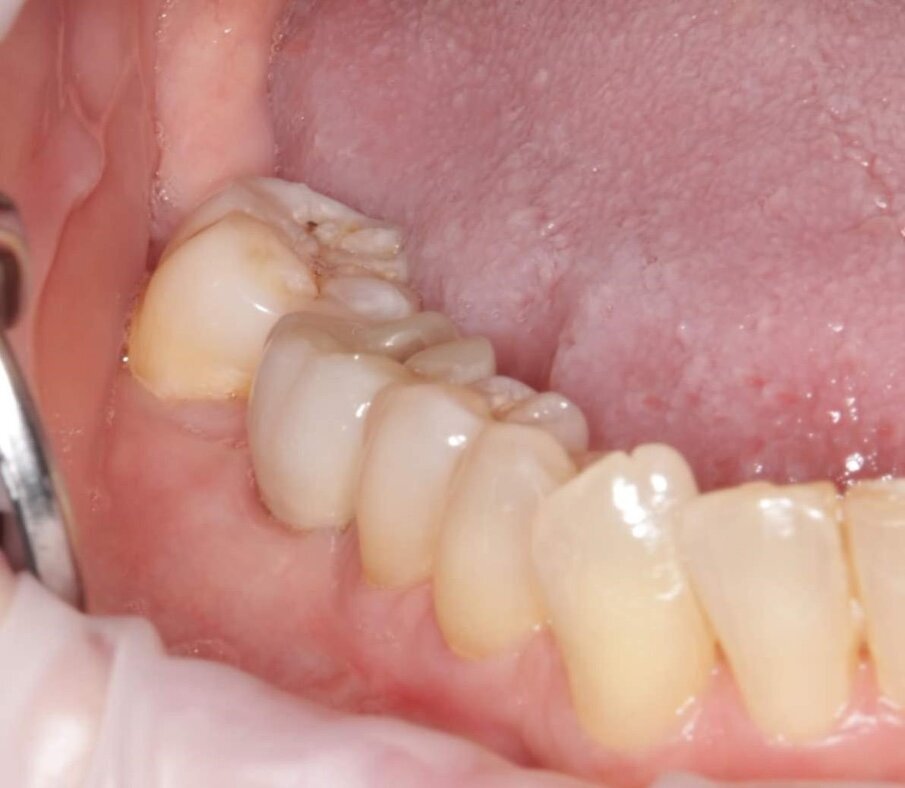

Nel caso 2, il tessuto cheratinizzato è stato preservato anche sui lati vestibolare e linguale a T2 e i valori dell’altezza del complesso sovracrestale erano identici a quelli registrati nel caso 1 (Fig. 26). Per quanto riguarda la valutazione a T3 e dopo l’inserimento di una corona monolitica in zirconia completa a 4 mesi, è evidente che è stata preservata una mimica del profilo cervicale del tessuto molle con conservazione del tessuto cheratinizzato (Fig. 27). Infine, sono state effettuate impronte digitali intraorali utilizzando lo scanner intraorale iTero (Align Technology), a T1 e a T3. I file STL (standard tessellation language) sono stati esportati nel software DTX Studio Clinic (Envista) per la comparazione nel tempo. Sulla base di un algoritmo di informazioni reciproche, le scansioni sono state sovrapposte automaticamente e un codice a colori ha mostrato le aree di differenza (Fig. 27).

Fig. 27_Risultato clinico del sito 46 con corona in zirconia in situ dopo 2 anni e 7 mesi.